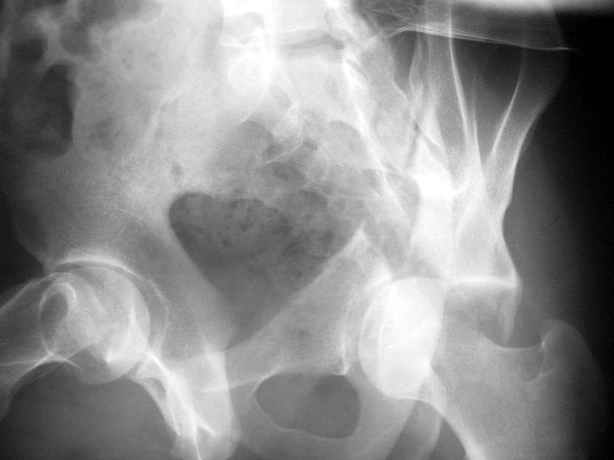

Высылаю пример еще одного случая, остеосинтез пластиной из подвздошного доступа.

Анатолий, во второй презентации, какой Ваш диагноз, не поперечный ли перелом ацетабулум? Вы написали, Ваш доступ был подвздошный, по моему мнению, ваш доступ лимитировал Вас к anterior column и постоянно надо было держать в контроле за натяжением femoral artery and vein, иначе грозит закупоркой артерии или вены, (были и такие experience), при сгибании в тазобедренном суставе, которое ухудшает и так ухудшенный доступ. По-моему, если доступ расширить, т.е. formal Ilioinguinal approach то применить пластину подлиннее 12-14 дырок на pelvic brim, через первое окно Ilioinguinal approach, т.е. Symphisis side, после рассечения места прекрепления muscle rectus abdominus, где достаточно места для 4 шурупов, тогда таким образом фиксированный перелом держится более стабильно и 4.5 мм шурупы для колонн можно было бы пропустить через пластину кзади впадины.